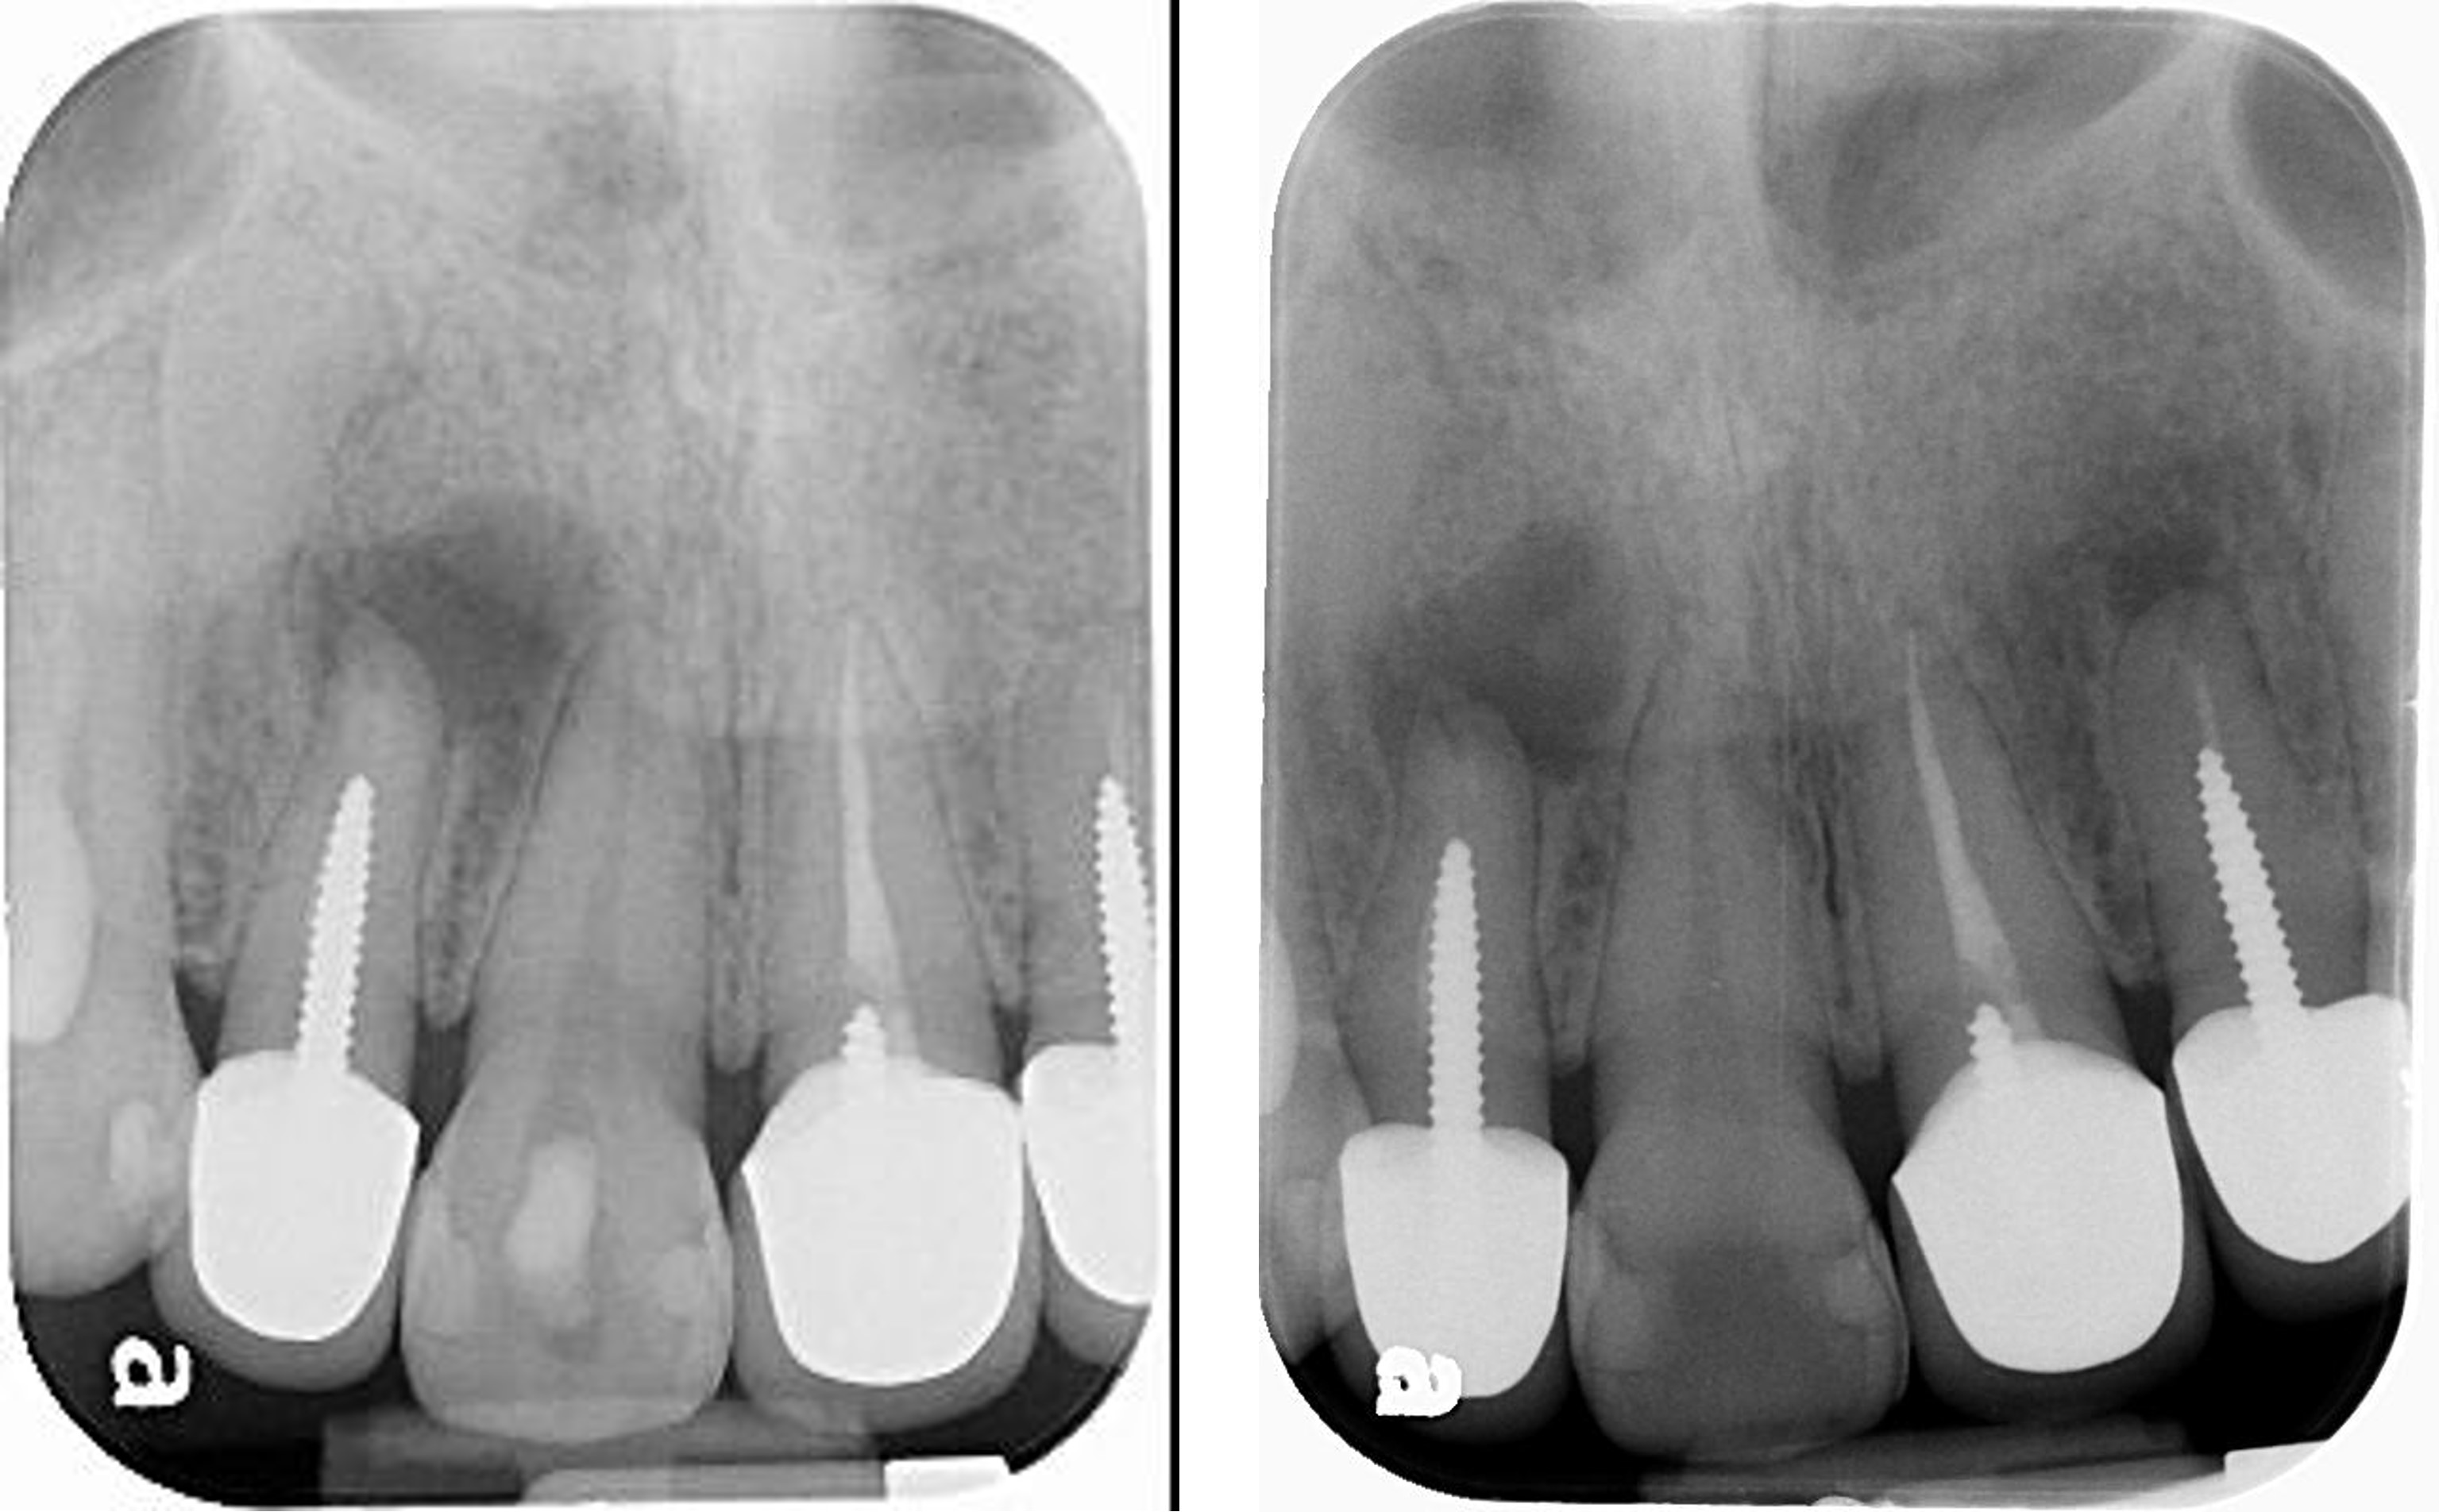

X光照相為牙科治療的必要步驟。 X光相片的種類分為 : (一 ) 咬冀 X光相片 ( BITEWlNG X-MYS ) 顯示出牙冠部份,包括上顎及下顎的牙齒在同一相 片內。特別用來顯示牙齒接縫之間的蛀牙,早期牙 週疾病的骨骼軟化缺失。 (二) 牙根尖 X光相片 (PERlAPICAL X-RAYS ) 顯示出整個牙齒、牙冠、牙根尖及牙齒周圍的骨骼 組織。顯示出牙齒蛀牙深淺程度,蛀洞是否侵入神 經管?阻生牙的位置方向,牙根是否斷裂、殘留牙 根? (三) 咬合面 X光相片 (OCCLUSAL X-RAYS ) 顯示出整個咬合面的上顎牙齒、或整咬合面的下顎 牙齒,可發現阻生牙、膿胞、囊腫。